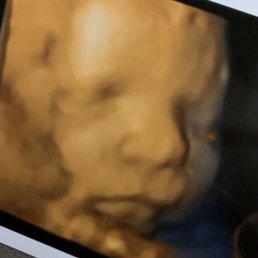

BEST TO DETERMINE THE. Modestos first center to offer the all new HD ultrasound. Peek A Baby understands the importance of family.

The Best 3D 4D and now all new HD in Modesto. What are you looking for. Modestos first center to offer the all new HD ultrasound.

The Best 3D 4D and now all new HD in Modesto. 1524 Mchenry Ave 100 Modesto CA. Get reviews hours directions coupons and more for Peek A Baby.